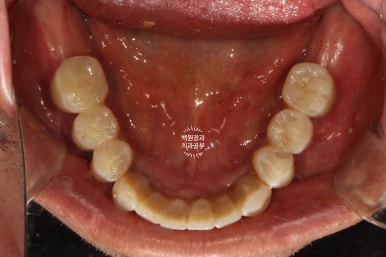

씹는면에서 본 임시치아입니다.

이제 제법 치아의 모양을 갖췄네요. 여기까지 오는데 7개월이라는 시간이 걸렸습니다.

임시치아로 저작기능에 적응하시면,

이제 비로소 최종 임플란트 치아로 바꿔드리게 됩니다.